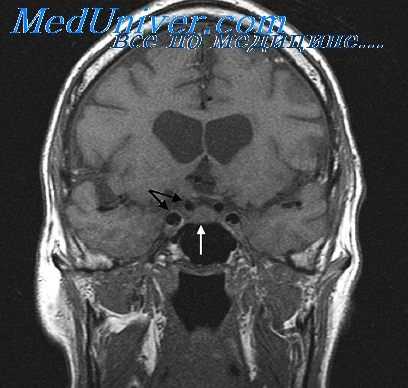

- Лучевые методы диагностики. По данным КТ височных костей может определяться деструкция сосцевидного отростка, исчезновение контуров пещеры среднего уха или наличие вместо нее узкого участка просветления с четкими границами, слияние антрума и аттика. При подозрении на синус-тромбоз выполняется синусография.